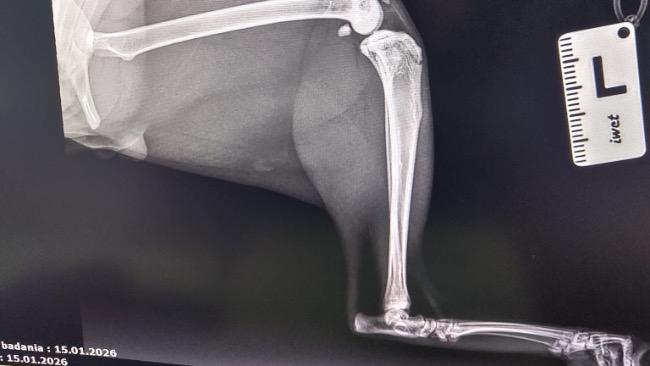

Zdiagnozowano u niego ciężką niestabilność obu rzepek, która sprawia, że każdy krok jest niepewny i bolesny. Dodatkowo lewa tylna kończyna wymaga specjalistycznego zabiegu TGR — wszczepienia protezy bloczka kości udowej.

To bardzo skomplikowana i kosztowna operacja, ale jedyna szansa, by Tymianek mógł normalnie chodzić i żyć bez cierpienia.

❗ Bez operacji jego stan będzie się tylko pogarszał!

Ból będzie narastał, pojawią się zwyrodnienia, a Tymianek — choć jeszcze taki młody — może zostać skazany na trwałe kalectwo. Już teraz widać, że ogranicza ruch, bo po prostu się boi.

🩺 Lekarze nie mają wątpliwości — czas ma tu ogromne znaczenie. Operacje stabilizacji obu rzepek oraz zabieg TGR muszą zostać wykonane możliwie szybko. Niestety ich koszt znacznie przekracza możliwości naszej fundacji. Dopóki nie zbierzemy chociaż części potrzebnej kwoty (która finalnie może okazać się wyższa), nie jesteśmy w stanie zapisać go na te zabiegi. 💔💔💔